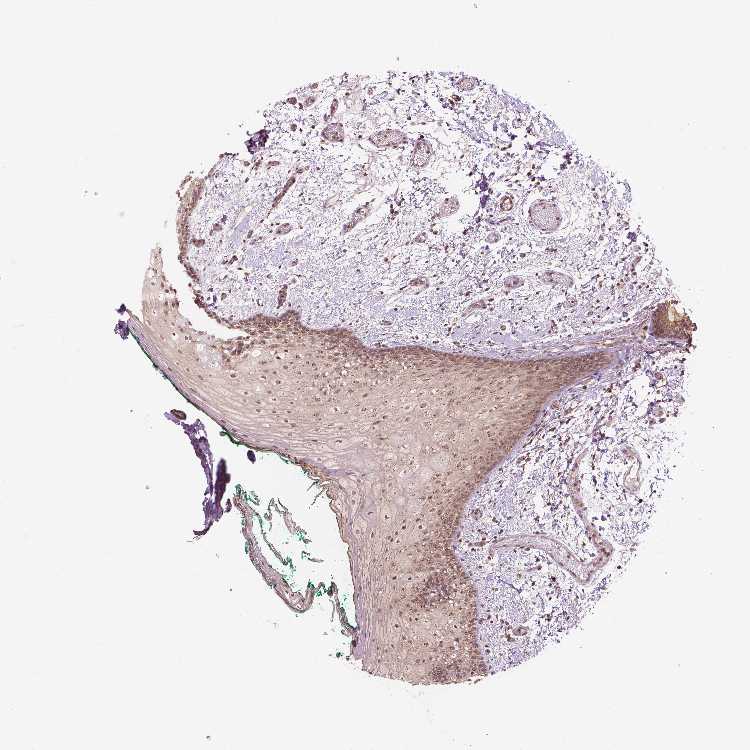

TISSUE PRIMARY DATA ORAL MUCOSA Show tissue menu

ORAL MUCOSA - Antibody stainingi

Antibody staining in the annotated cell types in the current human tissue is reported as not detected, low, medium, or high, based on conventional immunohistochemistry profiling in selected tissues. This score is based on the combination of the staining intensity and fraction of stained cells.

Each image is clickable and will lead to virtual microscopy that enables deeper exploration of all samples and also displays staining intensity scores, fraction scores and subcellular localization as well as patient and tissue information for each sample.

Antibody HPA065425Antibody CAB069426

Squamous epithelial cells MediumMedium